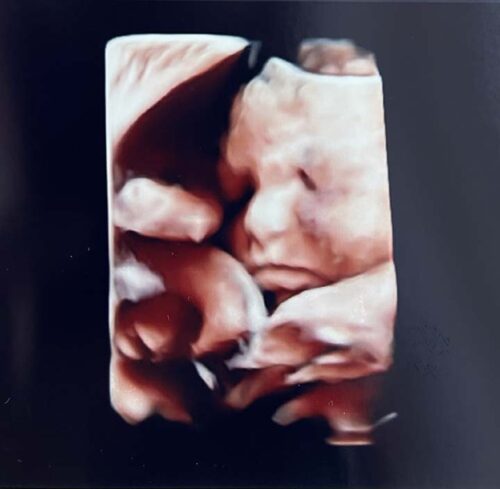

妊娠31週を明日から迎えられるお客さま。

予定日は3月末の春生まれの赤ちゃんです

体重は少し増えてきたものの、妊娠糖尿病や

妊娠高血圧の心配もなく、順調に過ごされて

います✨